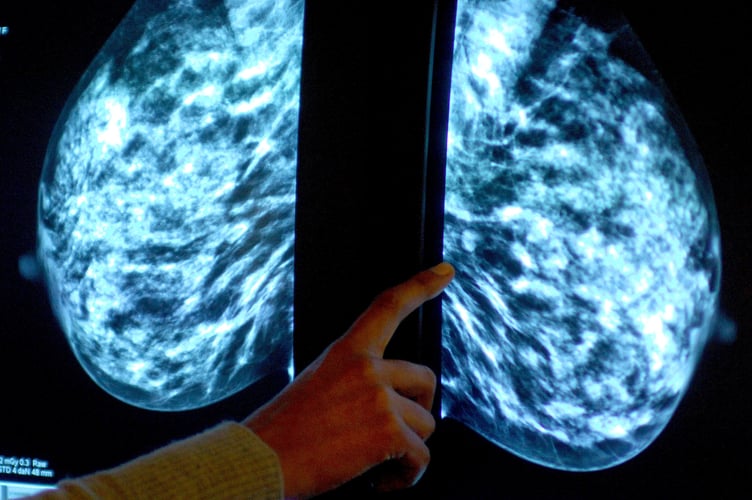

NHS England figures show 26,720 of the 39,150 people invited for a screening in the former NHS Somerset CCG had a test in the year to March this year.

It meant uptake of the screening stood at 68% – up from 67% the year before, but below pre-pandemic levels of 73% in 2019-20.

The figures show breast screening uptake across England increased to 65% last year from 63% in 2021-22. However, it remained well below pre-pandemic levels when 70% was recorded.